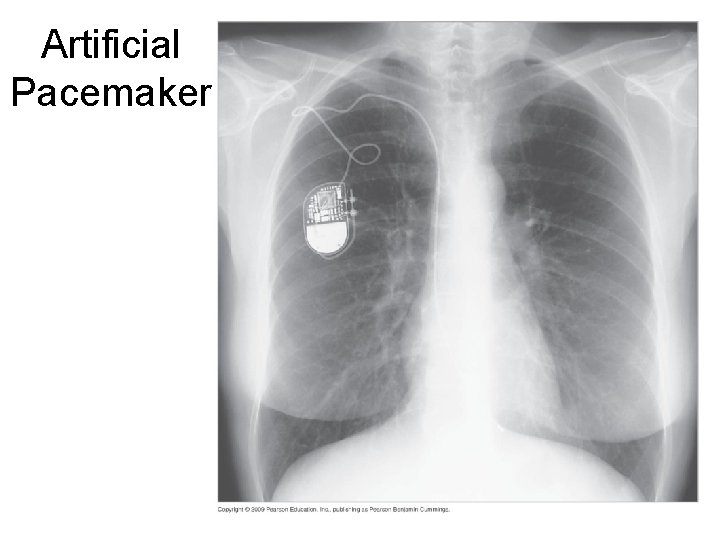

Artificial Pacemaker 37